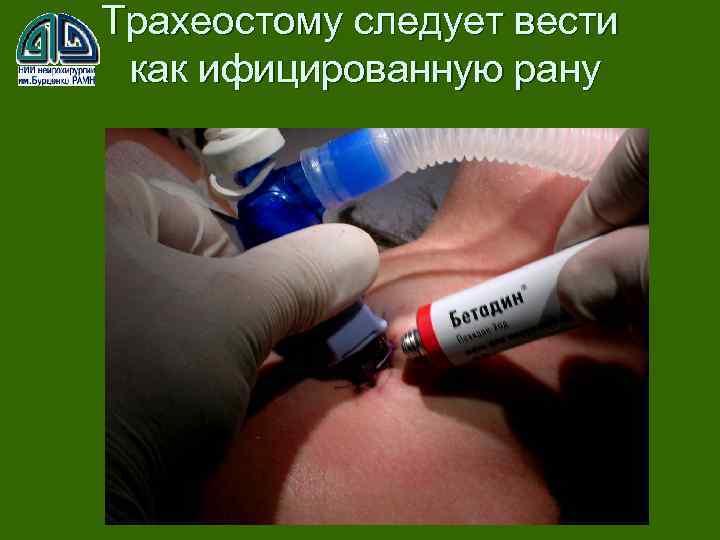

Состояние трахеостом может влиять на количество ВАП плохо хорошо

Состояние трахеостом может влиять на количество ВАП плохо хорошо

Трахеостому следует вести как ифицированную рану

Трахеостому следует вести как ифицированную рану